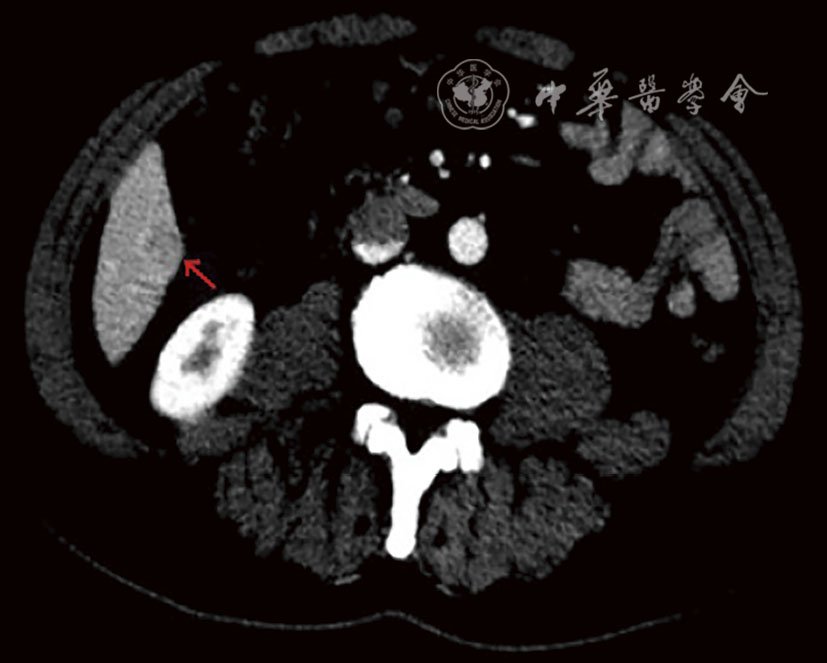

图1 一例同时性肝十二指肠乳头双原发癌CT图像 注:肝右叶下缘包膜下(肝S5/6)类圆形稍低密度影(红色箭头所示)